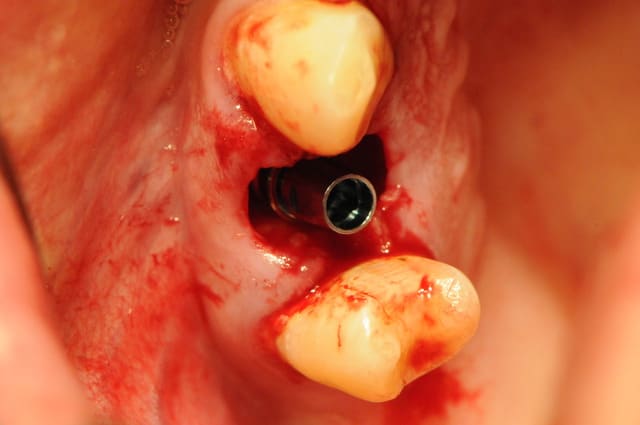

juste pour illustrer mon propos....

ici une MCI ou plutôt, devrais je dire une vis de cica anatomique immédiate.